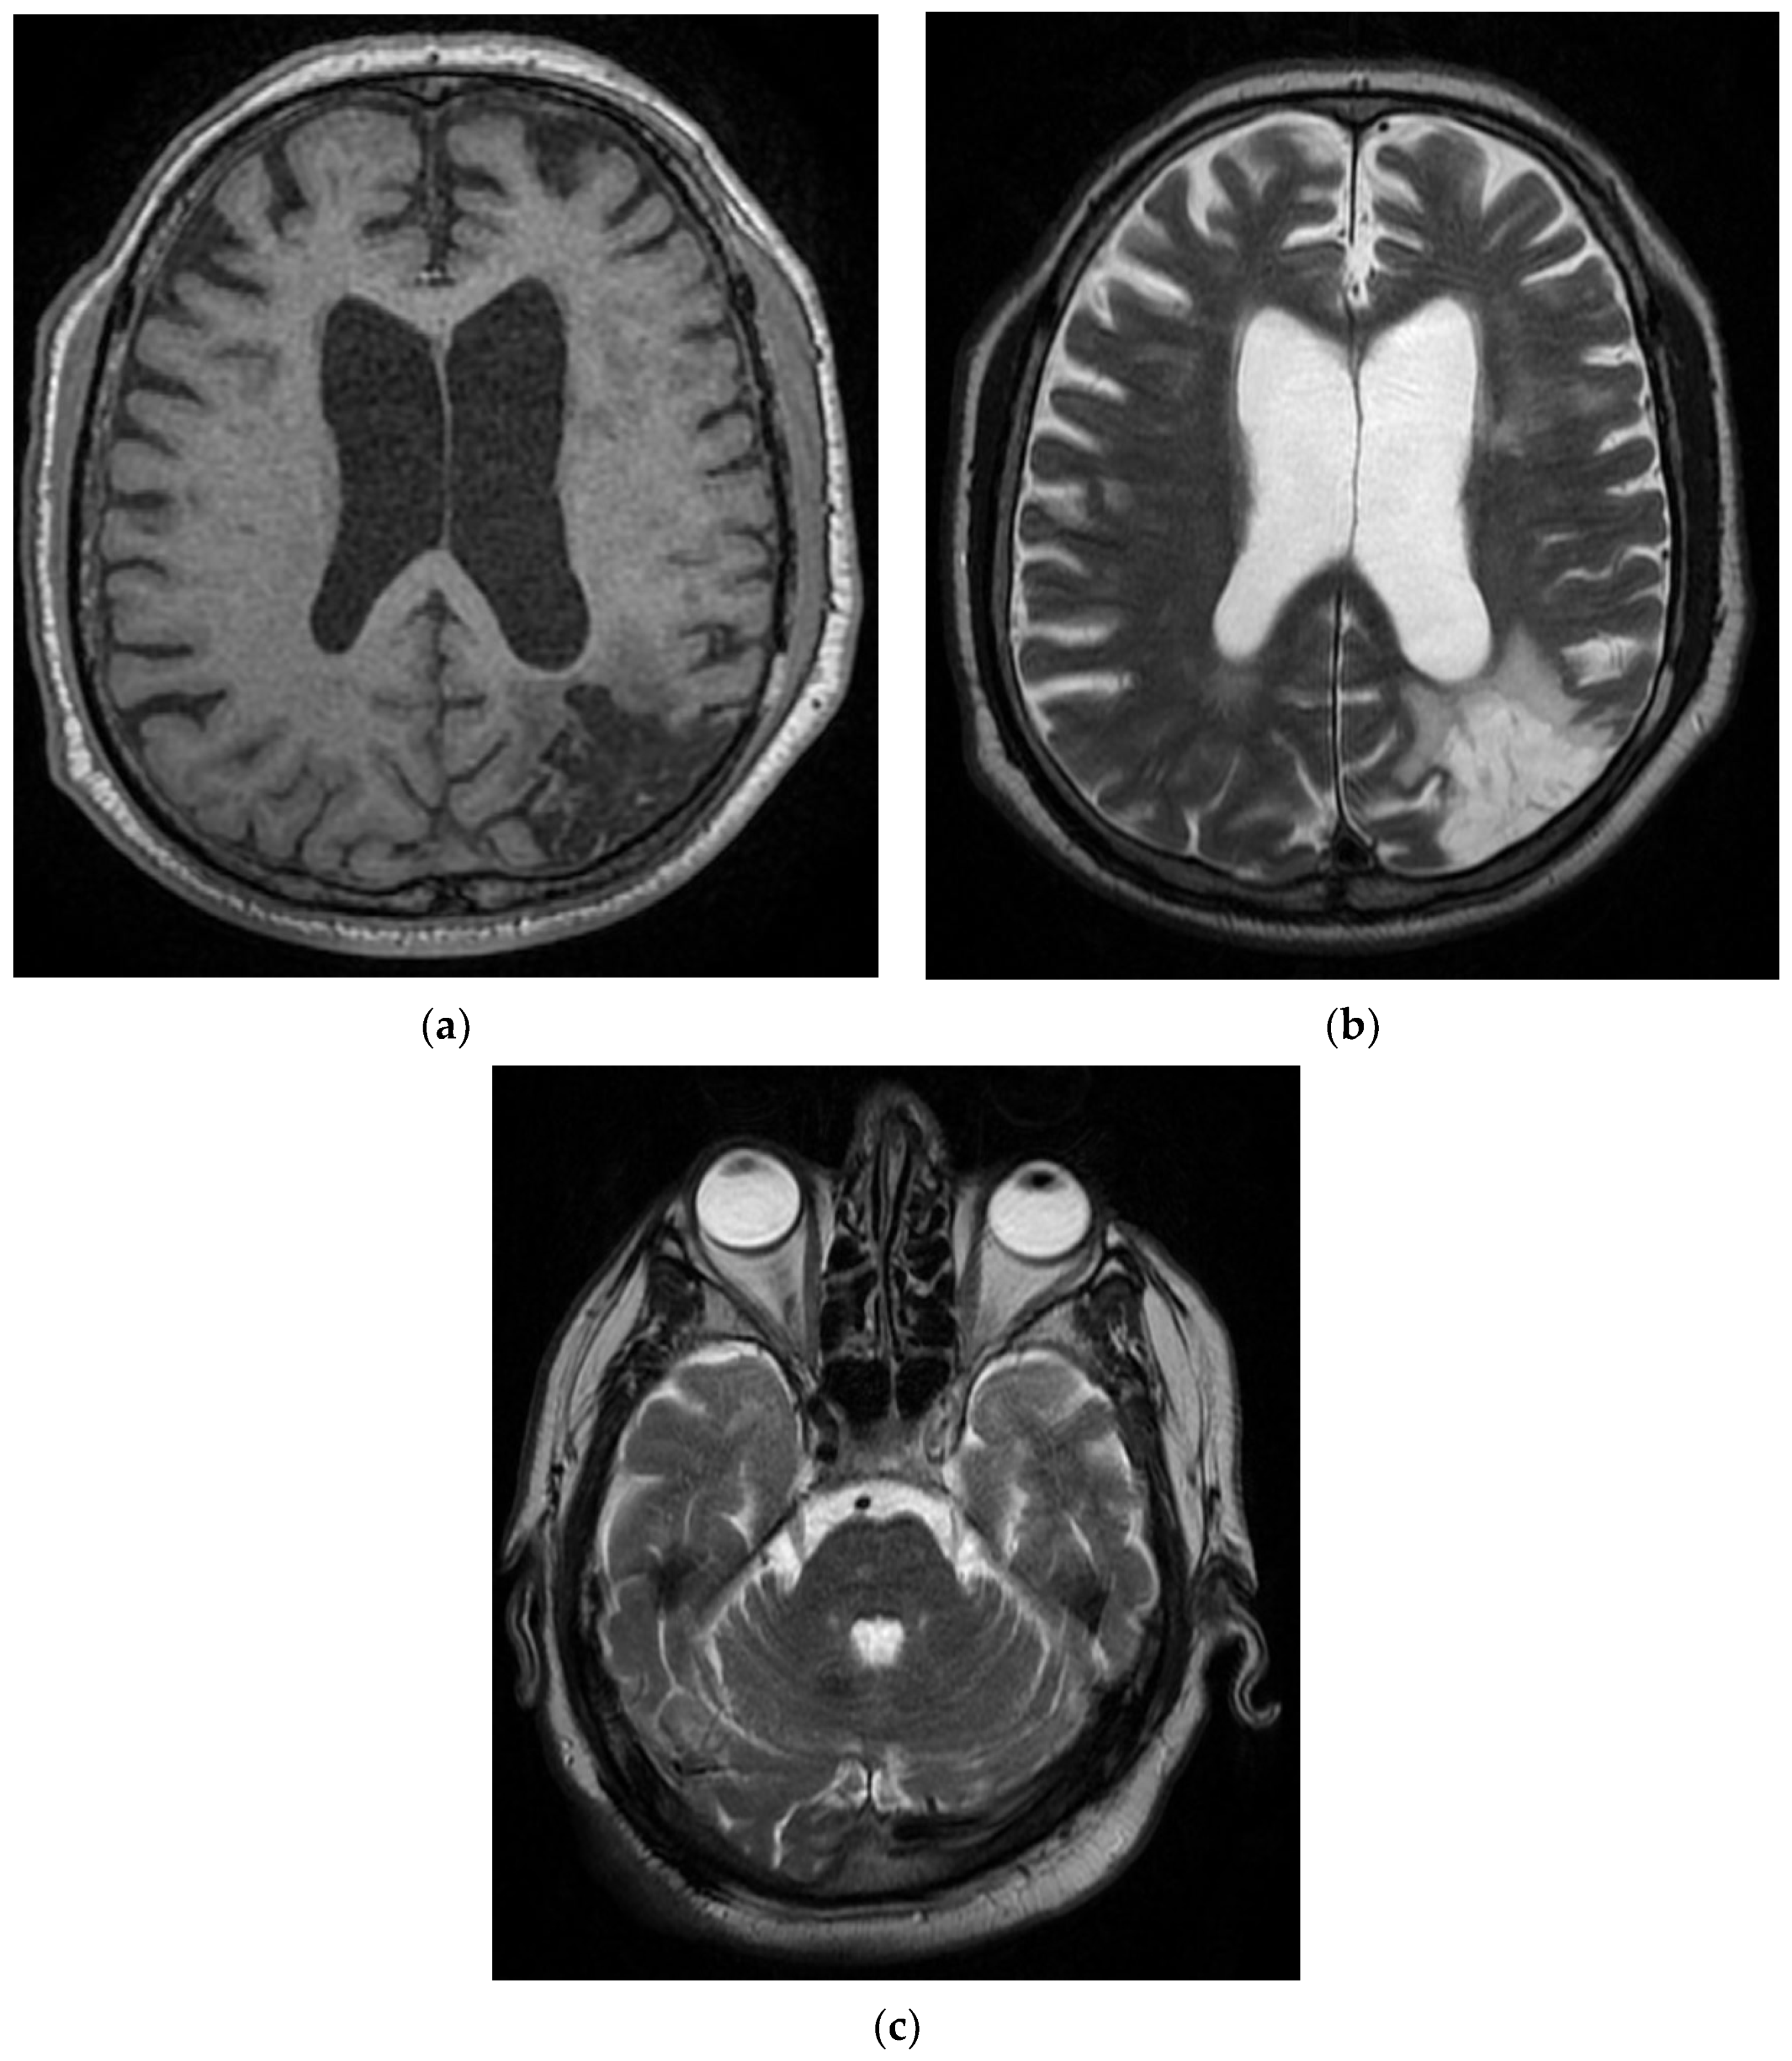

On day 6, the patient underwent a native brain MRI showing multiple infra- and juxta-centimetric lesions in hyper seminal T2/FLAIR, without diffusion restriction, bilaterally arranged in the hemispheric white matter subcortical frontal–temporal–parietal, as well as in the right cerebellar hemisphere and supratentorial demyelinating lesions, most likely with ischemic vascular substrate and linear and curvilinear tracts in a SWAN (susceptibility-weighted angiography)-like manner, and left-frontal and left-parietal cortical hemosiderosis (Figure 3).

Figure 3. MRI images of the Case 3 patient reveal multiple centimetric lesions in T2/FLAIR hypersignal (a,b), with no diffusion restriction, disposed in a white hemispheric substance in the bilateral subcortical frontal–temporal–parietal area, as well as in the right cerebellar hemisphere, and supratentorial demyelinating lesions most probably with an ischemic vascular sublayer. Additionally, linear and curvilinear traces in SWAN signal (c,d), disposed in the left cortical parietal, frontal area–frontal cortical and left parietal hemosiderosis.